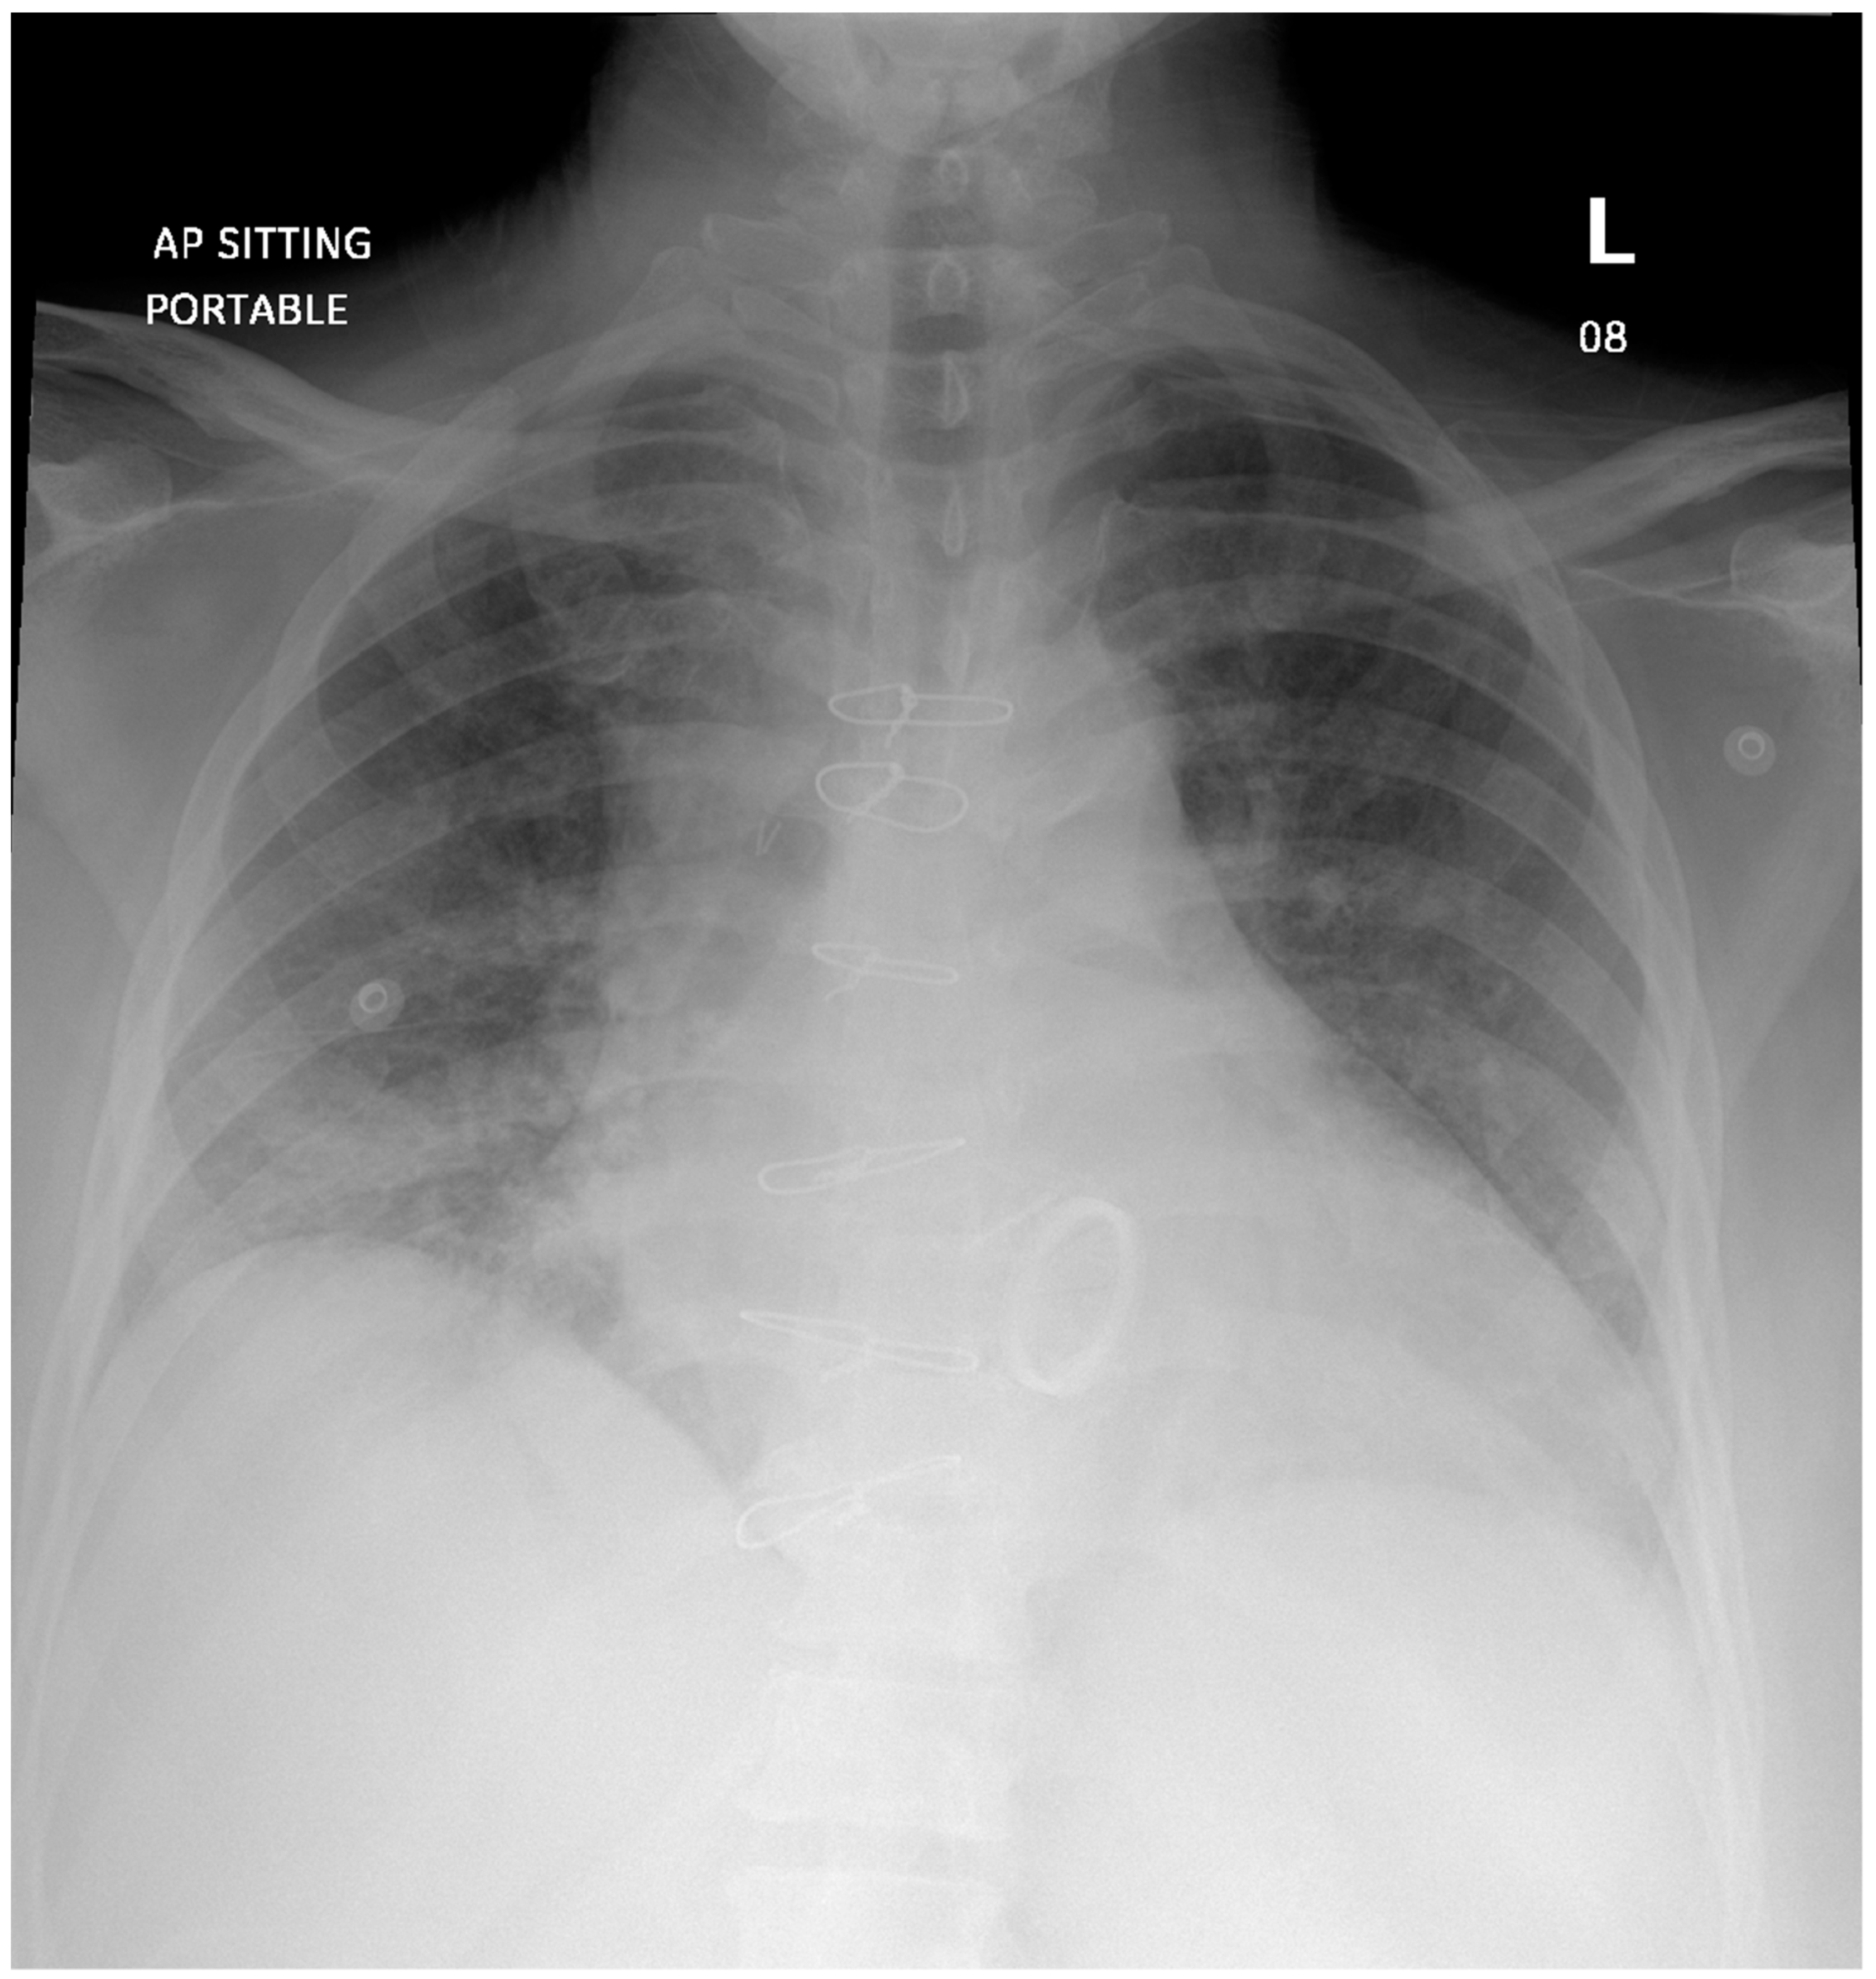

2. Case Presentation